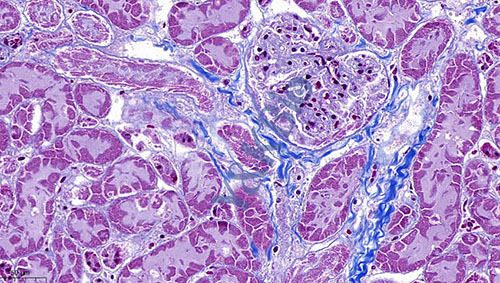

新疆Masson染色是病理染色服务中比较常见的一种,Masson染色用于胶原纤维和肌纤维的染色及鉴定;染色结果:胶原纤维呈蓝色、肌纤维呈红色、细胞核呈蓝黑色。

4.磷钼酸和磷钨酸在染色法中的作用各有不同,磷钼酸作用于胶原纤维,磷钨酸作用于纤维胶质,肌胶质,神经胶质和上皮纤维等。上述两种试剂的使用,可以促进组织有选择的染色,它们可以减少背景和核的染色,使背景清晰。